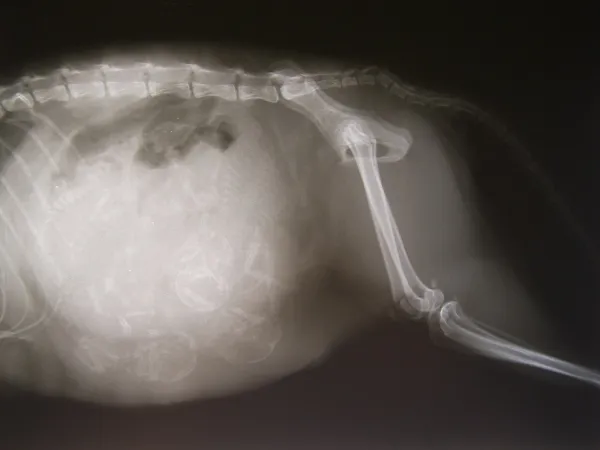

Les signes observables de gestation apparaissent progressivement, notamment l’augmentation du volume abdominal, le développement des mamelles et des changements comportementaux tels que la recherche de tranquillité ou des variations d’appétit. Pour confirmer la gestation, l’échographie est l’outil de référence dès le 21e jour, devenant pleinement fiable entre le 25e et le 28e jour. Une radiographie après le 50e jour permet de compter précisément les chiots avant la mise bas.

Des consultations régulières permettent de détecter précocement d’éventuelles complications, telles que la métrite, l’éclampsie ou les infections. Les vétérinaires recommandent un suivi échographique au premier tiers de la gestation et une radiographie au dernier tiers. Toute perte d’appétit prolongée, vomissement sévère ou saignement inhabituel doit motiver une consultation en urgence.

Radiographie de gestation de l’arrière-train d’une chienne gravide. Source : wikipedia.org

Pendant l’accouchement, la mère déchire la poche, coupe le cordon et lèche ses chiots pour stimuler leur respiration. En cas d’inexpérience, il peut être nécessaire d’ouvrir la poche, sécher le chiot et désinfecter le cordon. Les placentas sont généralement expulsés à chaque naissance et souvent consommés par la chienne, ce qui est normal. Une radiographie de fin de mise bas permet de vérifier qu’aucun chiot n’a été retenu. Dans les heures qui suivent, une surveillance attentive est essentielle : fièvre, pertes malodorantes, douleur ou apathie doivent conduire à une consultation vétérinaire, car ils peuvent révéler une infection ou une complication post-partum.